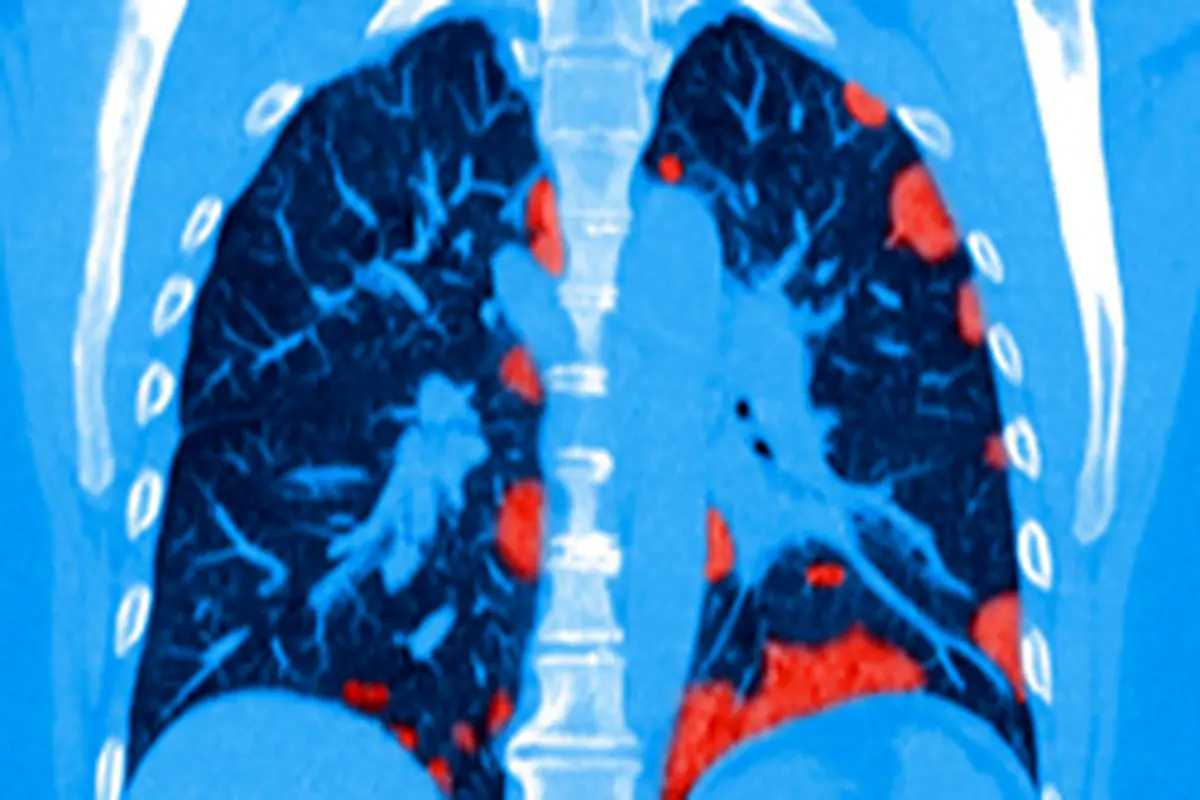

ویدئویی از تاثیر وحشتناک ویروس کرونا بر ریه بیماران

پارسینه: ویدئویی عبرتآموز از تاثیر وحشتناک ویروس کرونا روی ریه بیماران مبتلا را مشاهده می کنید.

این بیماری در شرایط حاد خود بسیار دردناک و کشنده است. به تازگی ویدئویی در فضای مجازی منتشر شده است که سیتیاسکن ریه یک بیمار مبتلا به کرونا را نشان میدهد. در این ویدئو شیوع بیماری کرونا در ریههای فرد مذکور شبیه گسترش موج یک انفجار مهیب است.

در ادامه میتوانید ویدئوی عبرت آموز ریه بیمار مبتلا به کرونا را مشاهده کنید:

در ادامه میتوانید ویدئوی عبرت آموز ریه بیمار مبتلا به کرونا را مشاهده کنید: